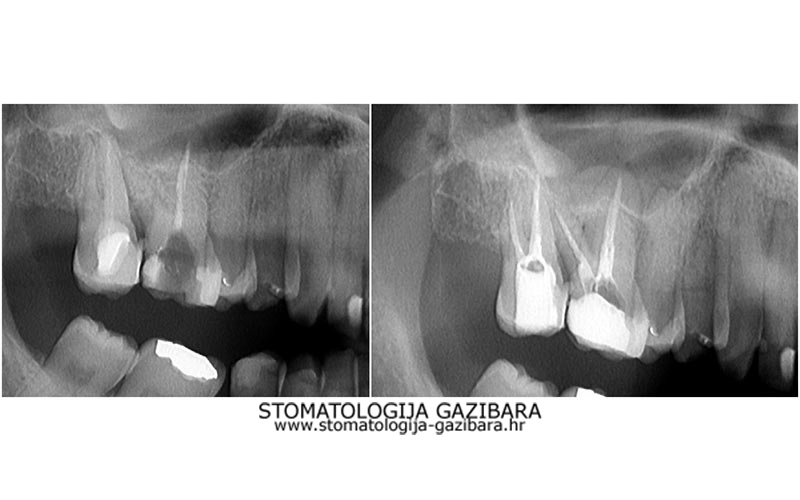

LIJEVO: 1a početno stanje,prednji zubi - DESNO: 1b nakon završetka terapijee LIJEVO: 2a revizija punjenja korijenskih kanala,višekorijenski zubi        <br />

DESNO: 2b nakon završetka terapije LIJEVO: 3a  prije revizije punjenja,jednokorijenski zub<br />

DESNO: 3b  nakon završetka terapije LIJEVO: 4a liječenje granuloma ,početno stanje<br />

SREDINA: 4b stanje nakon 9 mjeseci<br />

DESNO: 4c stanje nakon 3 godine, granuloma više nema !